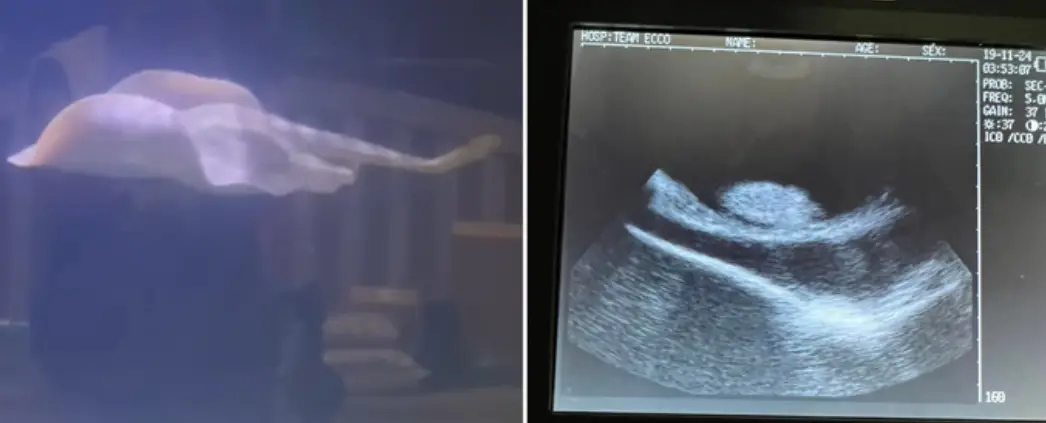

“Entonces pensamos que esa podría ser una posibilidad y decidimos hacerle una ecografía. Y vimos todos estos bultos dentro de ella, por lo que decidimos enviarles a dos personas con las que trabajamos las imágenes de ultrasonido”, añadio.

La respuesta de estos expertos fue: “Que estábamos viendo huevos, no quistes”, dijo Boyette. ¿Peró cómo se explicaría este fenómeno?